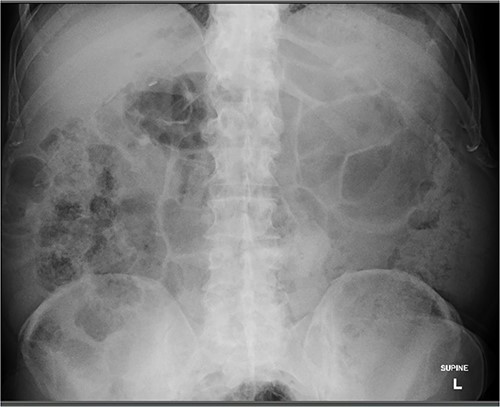

An 80 year old male presented to the emergency department after accidentally swallowing his hearing aids. On presentation he was pain free, hemodynamically stable, and had a soft abdomen. He had a background of type-2 diabetes, rheumatoid arthritis and diverticulitis. The hearing aids were powered by lithium battery. X-ray found two foreign bodies in the left upper abdomen (Fig. 1). After assessment in the emergency department, he returned home to await their natural passage. One hearing aid was found in his stools the following day, but he represented three weeks later as the second hearing aid remained unaccounted for. He underwent repeat abdominal x-ray and CT, which found the hearing aid retained within a presumed distal duodenal diverticulum (Figs 2 and 3). He was booked a push enteroscopy the following day.

Abdominal CT identifying one hearing aid in a jejunal diverticulum 3 weeks after initial presentation – coronal view.